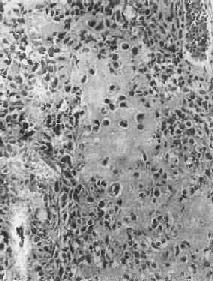

图17-3 骨软骨瘤 图示特征性的三层结构,即最表浅的纤维层,中间的软骨层(软骨帽)和深部的松质骨 【临床病理联系】 骨软骨瘤一般无明显症状,只是局部肿块形成。有时肿块压迫周围组织,引起疼痛和不适。如果肿块体积迅速增大,软骨帽增厚至1cm以上,则须考虑恶变的可能,这在多发性者比单发性者多见。本瘤如手术切除不彻底,则易复发,多发生在1年或数年后。 (二)软骨肉瘤 软骨肉瘤(chondrosarcoma)是从软骨细胞发生的原发性恶性骨肿瘤,由肿瘤性软骨细胞及软骨基质组成。软骨肉瘤是颇为常见的恶性骨肿瘤,其发病率仅次于骨肉瘤,其发病年龄多在中年以后,多见于40~70岁,根据发病部位不同,可分为中央型及周围型两种。中央型从骨髓腔发生,肿瘤为骨皮质所包绕或穿破骨皮质,多见于长管状骨,特别是股骨和胫骨;周围型从骨肿瘤表层出发,向周围软组织及骨皮质侵犯,多见于骨盆、肩胛骨及肋骨等。少数软骨肉瘤来自软骨瘤和骨软骨瘤之恶变。 【病理变化】 肉眼观,中央型软骨肉瘤主要发生在骨髓腔内,呈灰白色、半透明的分叶状肿物,其中常见淡黄色的钙化或骨化小灶。这些钙化或骨化小灶在X线片上可以看到,对诊断软骨肉瘤很有帮助,但高度恶性的软骨肉瘤钙化常不明显。随肿瘤的增大可使骨髓腔变大并侵犯骨皮质,骨外膜受刺激后,可有反应性新骨形成,使受累骨皮质增厚。恶性程度较高的软骨肉瘤,在早期即可穿破骨皮质,向软组织内扩展,形成较大的肿块,周围没有新骨形成。外围型软骨肉瘤瘤体主要在骨外,其表面被覆一层薄而不完整的包膜。以上两型软骨肉瘤均常发生粘液变、出血及囊性变等继发性变化。 镜下观,肿瘤的分化程度差异很大,分化好的软骨肉瘤在镜下易误诊为软骨瘤,但在肿瘤的边缘可以找到瘤细胞的异型性,如核肥大、深染,出现较多的双核、巨核和多核瘤巨细胞,并可见明显核仁(图17-4)。在分化差的软骨肉瘤则上述瘤细胞的异型性很明显,核分裂像也多见。软骨肉瘤的基质可为与一般透明软骨相似的透明基质,也可为粘液样基质,常见于恶性程度高的软骨肉瘤。

图17-4 软骨肉瘤 软骨细胞大小不等,有的较大。许多细胞有肥硕的胞核,有的有双核 【临床病理联系】 局部疼痛及肿块往往是软骨肉瘤的主要症状。近关节的肿瘤常影响关节活动。盆骨的巨大软骨肉瘤可压迫邻近器官,引起相应症状。软骨肉瘤的分化程度对临床经过有一定影响,分化较好的软骨肉瘤往往生长较慢,预后较好。软骨肉瘤一般比骨肉瘤生长慢,转移也较晚。血道转移可至肺、肝、肾及脑等处,淋巴结转移极罕见。软骨肉瘤术后常易复发,多次复发常使恶性程度增加。 (三)骨巨细胞瘤 骨巨细胞瘤(giant cell tumor of bone)是一种具有局部侵袭性及复发倾向的原发性骨肿瘤。由梭形和卵圆形的基质细胞(stromal cell)及大量散布在其间的多核巨细胞组成,肿瘤间质富于血管。由于本瘤内有大量多核巨细胞,因而称为巨细胞瘤;又因过去认为这些多核巨细胞是破骨细胞,故也称为破骨细胞瘤(osteoclastoma)。本瘤的组织来源未明,以上各名称纯系形态学的描述性命名。在我国骨巨细胞瘤的发病率较高,仅次于骨软骨瘤和骨肉瘤,居第三位。本瘤好发年龄为20~40岁的青壮年,性别无明显差异。 【病理变化】 骨巨细胞瘤多发生于四肢长骨的骨骺端,尤以股骨下端及胫骨上端为多见,约占半数左右,其次为桡骨下端、尺骨下端或肱骨上端等部位。长骨以外则以脊椎为多见。 肉眼观,本瘤常侵犯骨骺线已闭合的长骨端,大多数位于骨骺,早期常为偏心性生长,增大的肿瘤使骨皮质受累而向外膨胀。在肿瘤周围往往有菲薄的骨壳,乃由骨内、外膜反应性新生骨构成,肿瘤的境界比较清楚。肿瘤内原有松质骨大部分或全部消失,瘤内常有纤维组织或骨性间隔。由于肿瘤组织的溶骨性破坏,常造成病理性骨折(图17-5)。肿瘤组织呈灰红色,质软而脆,较大的肿瘤常合并出血及坏死,并伴有囊性变而形成大小不等的空腔,囊腔内含有浆液性或血性液体。晚期病例骨性包壳如果被破坏,则可侵犯软组织形成肿块。关节软骨有抗肿瘤浸润的作用,关节软骨下骨间质可完全被破坏,致使关节软骨失去支持而扭曲变形。